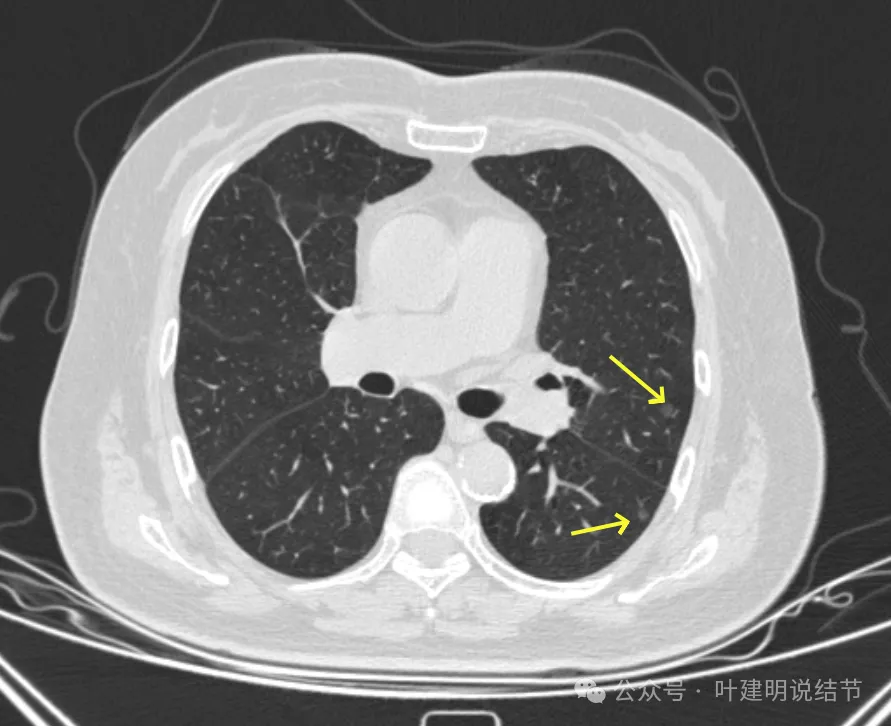

病灶31:左上叶磨玻璃结节,轮廓与边界清,灶内有偏实性成分,紧贴胸膜,此灶相对较为主要,考虑原位癌或微浸润性腺癌可能性较大。

病灶32:上叶尖后段胸膜下此灶密度较高,有小血管进入,但病灶本身还小,考虑原位癌可能性稍大。

病灶46:左下叶磨玻璃结节,轮廓较清,密度稍高,贴着胸膜,轮廓与边界清。

你的两肺我数了一下,较明显的多达48处结节,还有过小的或不太确切是结节的不算,但估计在随访中仍会是结节的。大部分都是淡磨玻璃结节,轮廓与边界较为清楚,没有显著实性成分。其中最大最主要的病灶是左上叶胸膜下的,此灶轮廓清楚,磨玻璃密度,贴着胸膜,灶内密度稍不均,但未见明显异常增粗的血管进入穿行,胸膜牵拉也不厉害,考虑仍是微浸润性腺癌或浸润性腺癌贴壁为主型的阶段,近期风险仍不大,何况两肺这么多病灶,即使切了主病灶也不能解决后续其他结节进展的问题。所以个人仍倾向在风险相对可控不大的情况下,继续随访。6-9个月复查应该是安全的,其实12个月复查也不见得就会有风险。待关注最主要的病灶有风险了,再来综合评估考虑干预事宜,包括如何干预,以及处理哪几处同侧病灶。意见供参考!